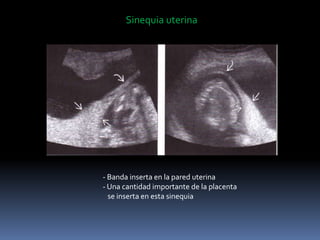

Sinequia uterina

- Banda inserta en la pared uterina

- Una cantidad importante de la placenta

se inserta en esta sinequia